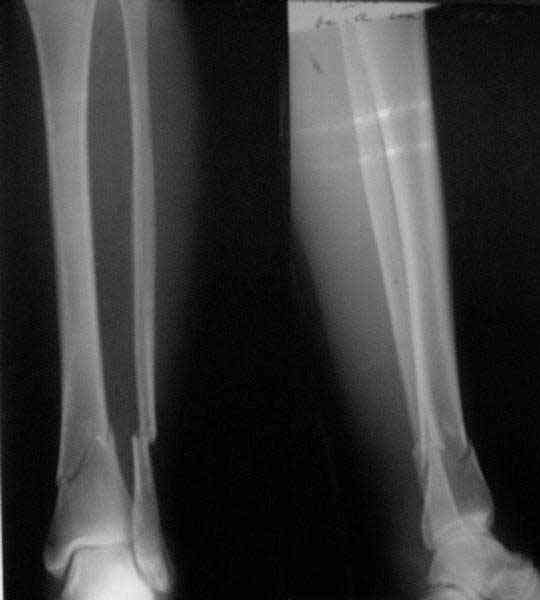

A typical case is attached, also an image with intra-op reduction obtained by a small wire distractor, in the moment of insertion a Poller wire in AP direction. Fixation by a SIGN nail. Despite the fibula was not fixed healing was obtained with the unchanged alignment.

Very interesting application, but is the final position in a little distal varus with some fibula

distraction? Would that have been eliminated by fibula plating?

TDVC> Very interesting application, but is the final position in a

TDVC> little distal varus with some fibula distraction?

At least both the ankle mortise and tibial alignment look acceptable, don't they?

TDVC> Would that have been eliminated by fibula plating?

I am just trying to illustrate that prevention of 1)tibial valgus and 2)loss of reduction can be provided without fibular plating. Small changes of conventional nailing techniques allow to maintain reduction of the tibia reliably without adjunctive fibular stabilization.

In delayed cases acute length restoration performed only in the tibia may leave the fibula shortened thus change the mortise. So it is reasonable to restore length of both bones simultaneously by distractor and fix the fibula not with open reduction and plating but just by a single perQ screw. Example attached.